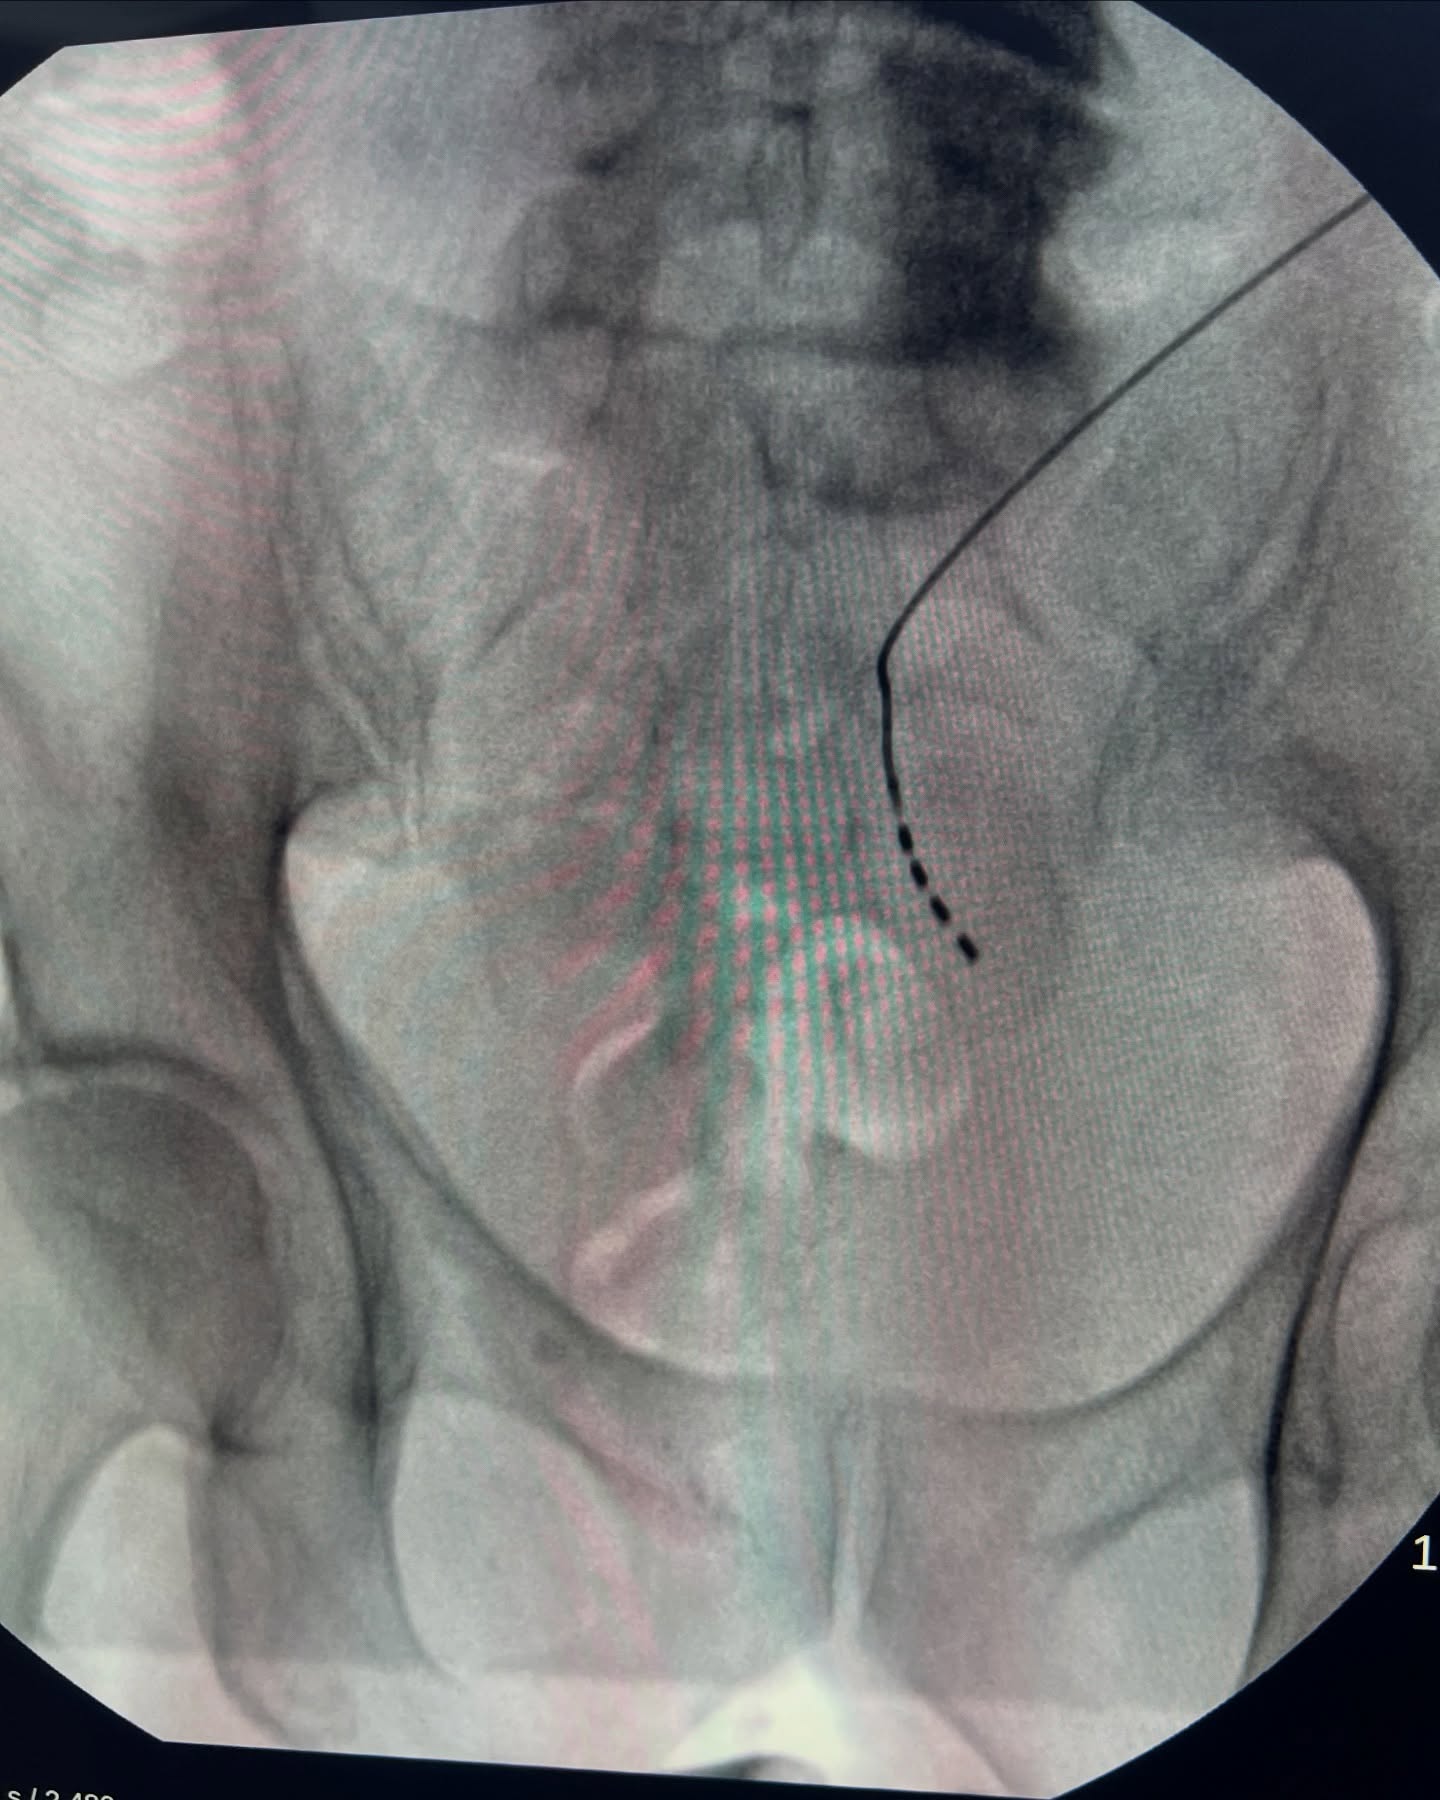

Neuromodulación sacral con InterStim – Tecnología de Medtronic

Implante utilizado en casos de retención urinaria no obstructiva y vejiga hiperactiva. Este sistema modula la señal nerviosa entre la vejiga y el sistema nervioso central, ayudando a recuperar el control urinario.

Hoy realizamos otra implantación del neuromodulador sacral InterStim™️ de Medtronic, fabricado en Villalba, Puerto Rico.

La neuromodulación sacral es un procedimiento mínimamente invasivo que ofrece mejoras significativas en la calidad de vida de quienes padecen estos trastornos.

El nuevo dispositivo InterStim™️ SureScan

- Es compatible con resonancia magnética nuclear (MRI).

- Tiene una duración de batería de hasta 10 años.

- Ofrece tecnología avanzada con excelentes resultados clínicos.